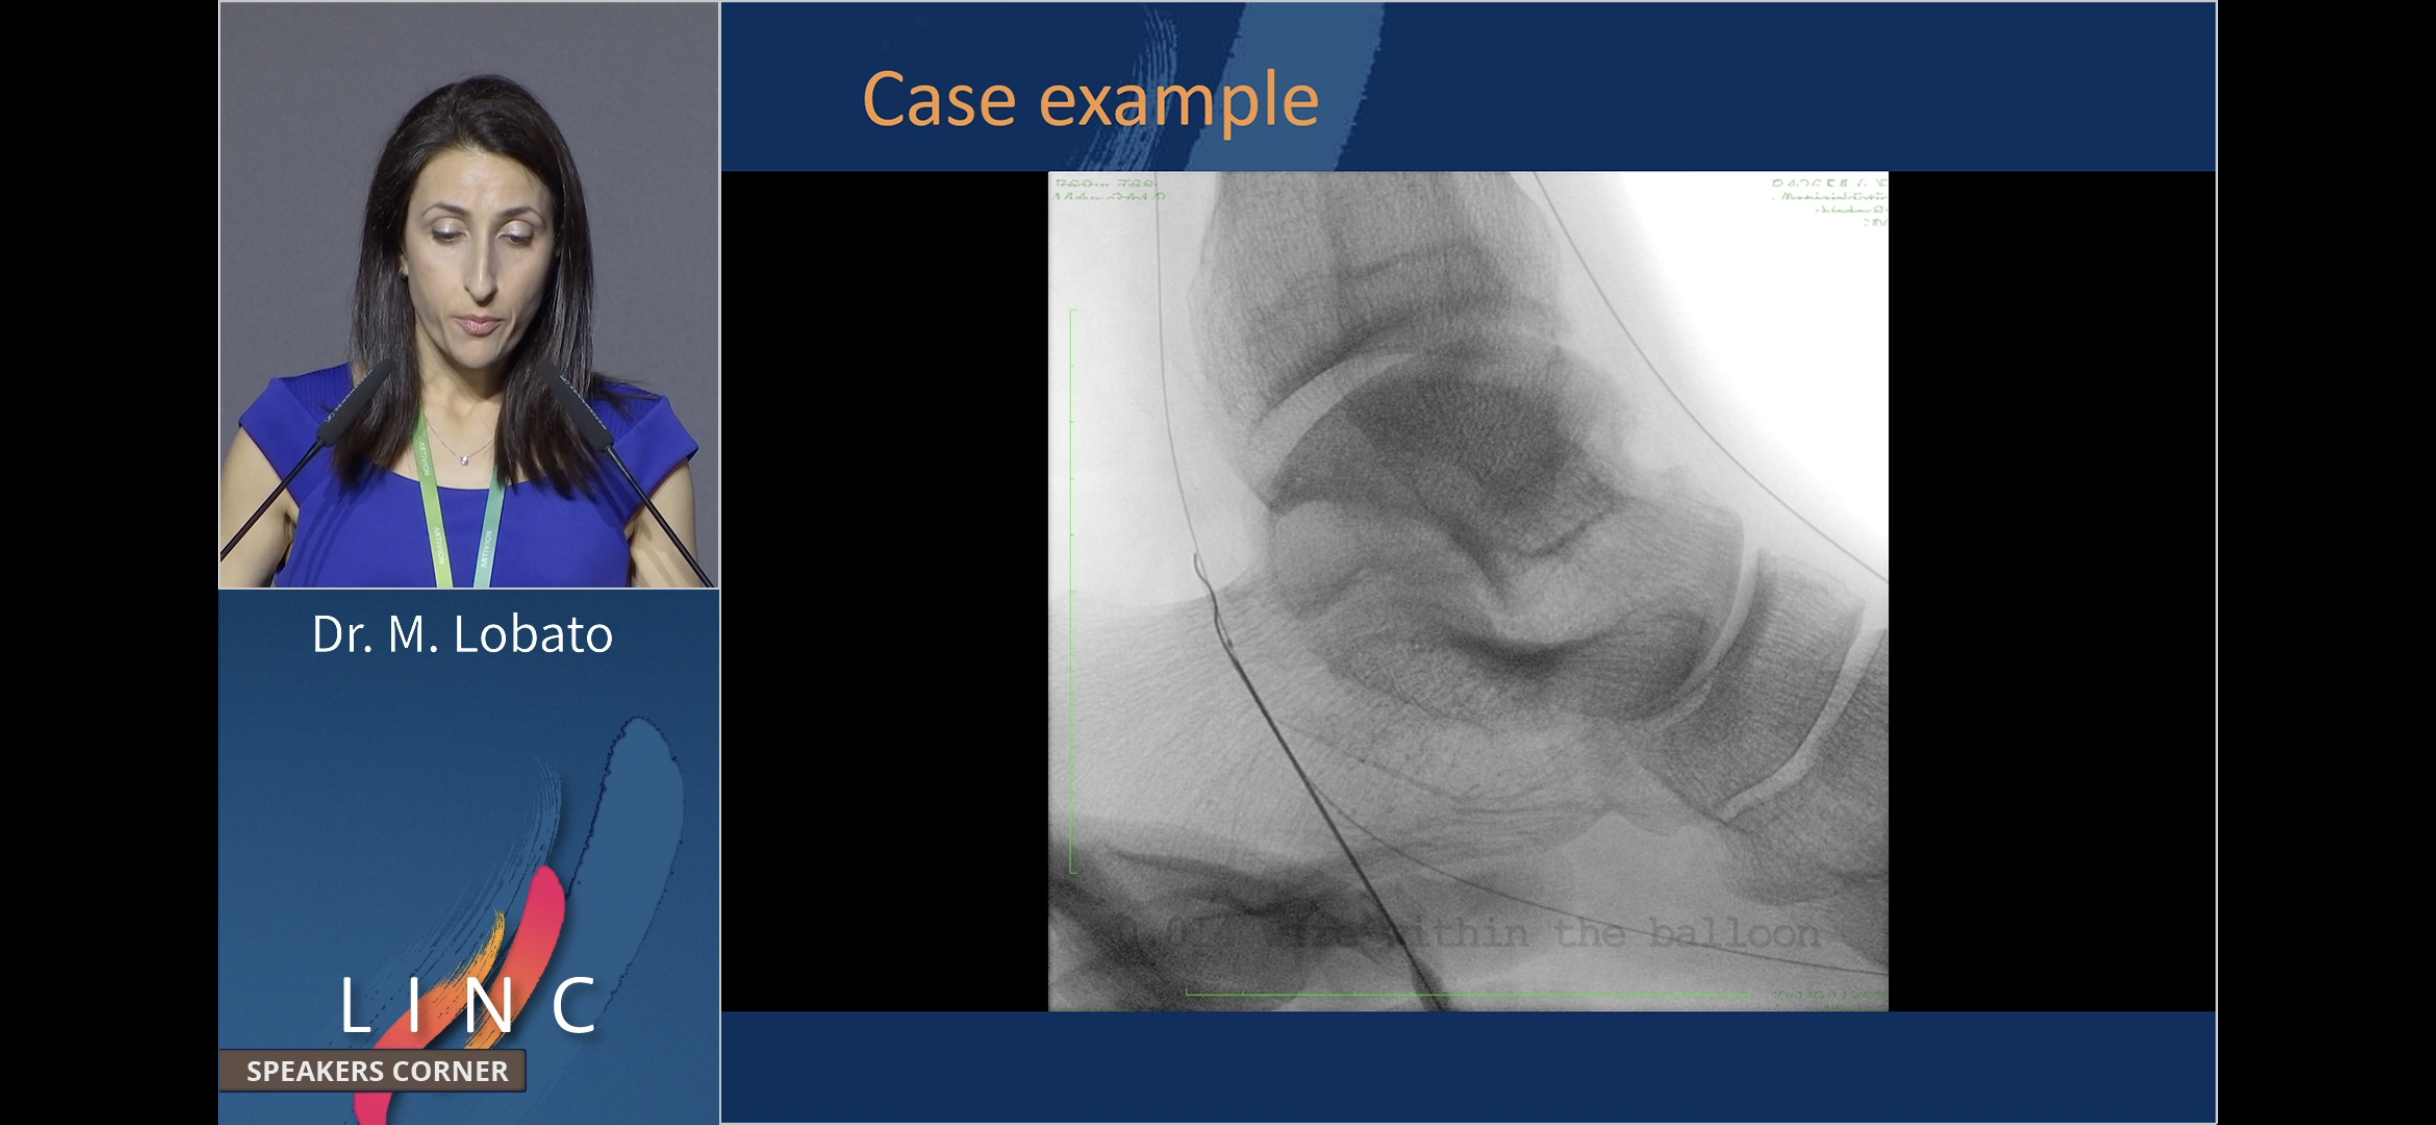

Balloon Assisted retrograde puncture. Marta Lobato. SC.

novel. They are puncturing into the balloon (antegrade) IN the foot to obtain more direct access across the arch.